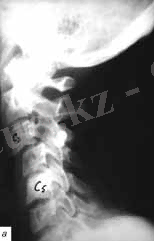

- Орналасуына байланысты мойын бөлімі (рис. 2, а) -

- С1 омыртқасының доғасының сынығы -Джеферсон сынығы

- С2 омыртқасының доғасының сынығы -хэнгман сынығы («асылған » сынық - рис. 2, б) ;

- С2 омыртқасының тісінің сынығы (рис. 2, в) -

Рис. 2. Омыртқаның мойын бөлімінің Рентгеногграммасы

а- схема, б - хэнгман сынығы ( «асылған »), в - С2 омыртқа тісінің сынығы